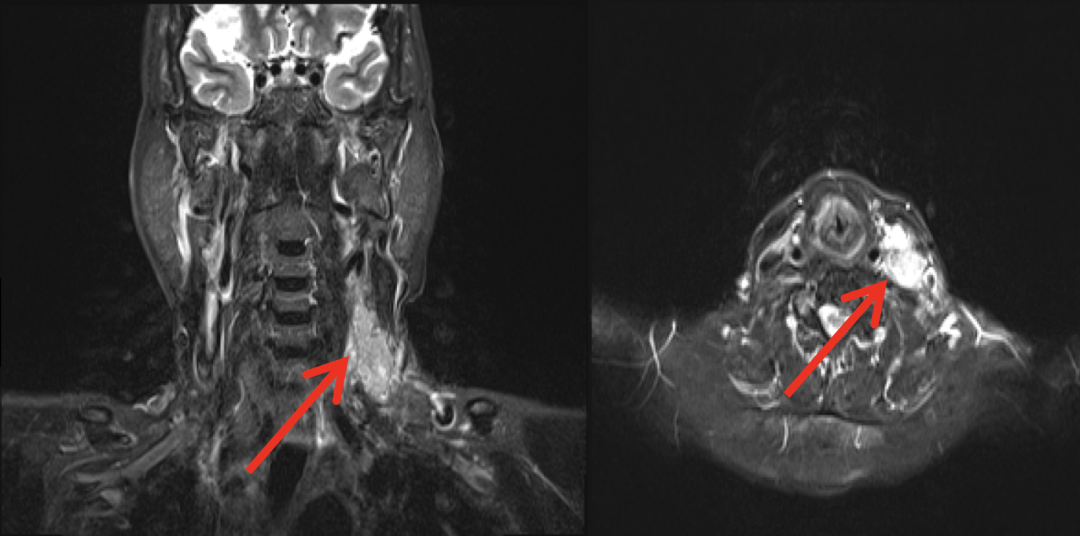

图片

2020年3月2日示左侧颈部肿块大小约1.5cm

疗效评价PR